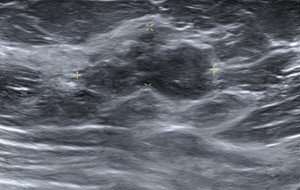

HALLAZGOS RADIOLÓGICOS